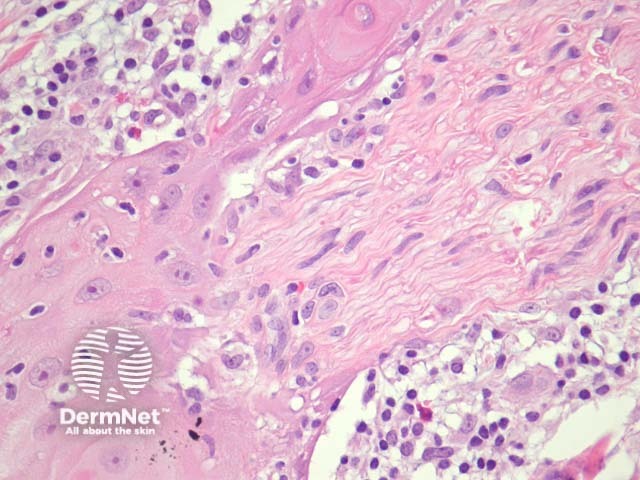

Typically SCC is graded as:

Grading of SCC depends on how easy it is to recognise the characteristics of squamous epithelium (eg. intracellular bridges, keratinisation), pleomorphism and mitotic activity. There is considerable inter-observer variation in grading SCC.